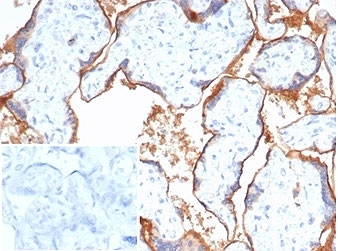

Immunohistochemistry analysis of PVRL4 / Nectin-4 antibody (clone NECT4/7271) in human placental tissue. Formalin-fixed, paraffin-embedded placenta demonstrates prominent membranous HRP-DAB brown staining outlining trophoblastic cells and chorionic villi, consistent with cell surface localization of PVRL4. Background staining is minimal, and nuclear counterstain highlights tissue architecture. The inset shows PBS used in place of primary antibody as a negative control, confirming absence of non-specific secondary antibody binding. Heat-induced epitope retrieval was performed by boiling tissue sections in pH 9 10 mM Tris with 1 mM EDTA for 20 minutes followed by cooling prior to staining.